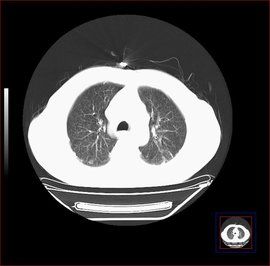

2. X 線與 CT : X 線胸片上病變多位於中下肺野,早期呈磨玻璃樣,周邊肺野常見播散性結節影,多發環狀影。晚期呈典型瀰漫性線條狀、結節狀、雲絮狀、網狀陰影、肺容積縮小,無肺門淋巴結腫大。

2. X 線檢查:早期呈毛玻璃狀,典型改變瀰漫性線條狀、結節狀、雲絮樣、網狀陰影、肺容積縮小。